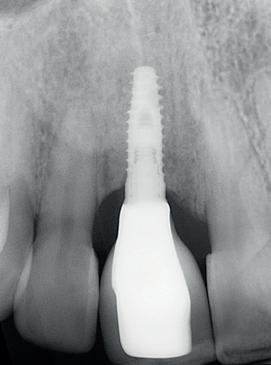

Na het klinische onderzoek volgde het röntgenologisch traject. De CBCT liet precies zien wat we al vreesden: een front waarin het bot onregelmatig was, duidelijke radiolucenties rond de pijlers en een infectiegebied dat zich onder vrijwel de gehele brug had verspreid. Tegelijkertijd was er ook potentie. Net voldoende botstructuur om immediate implantaatplaatsing te overwegen, mits alles perfect gepland zou worden.

4. Pre-chirurgische OPG.